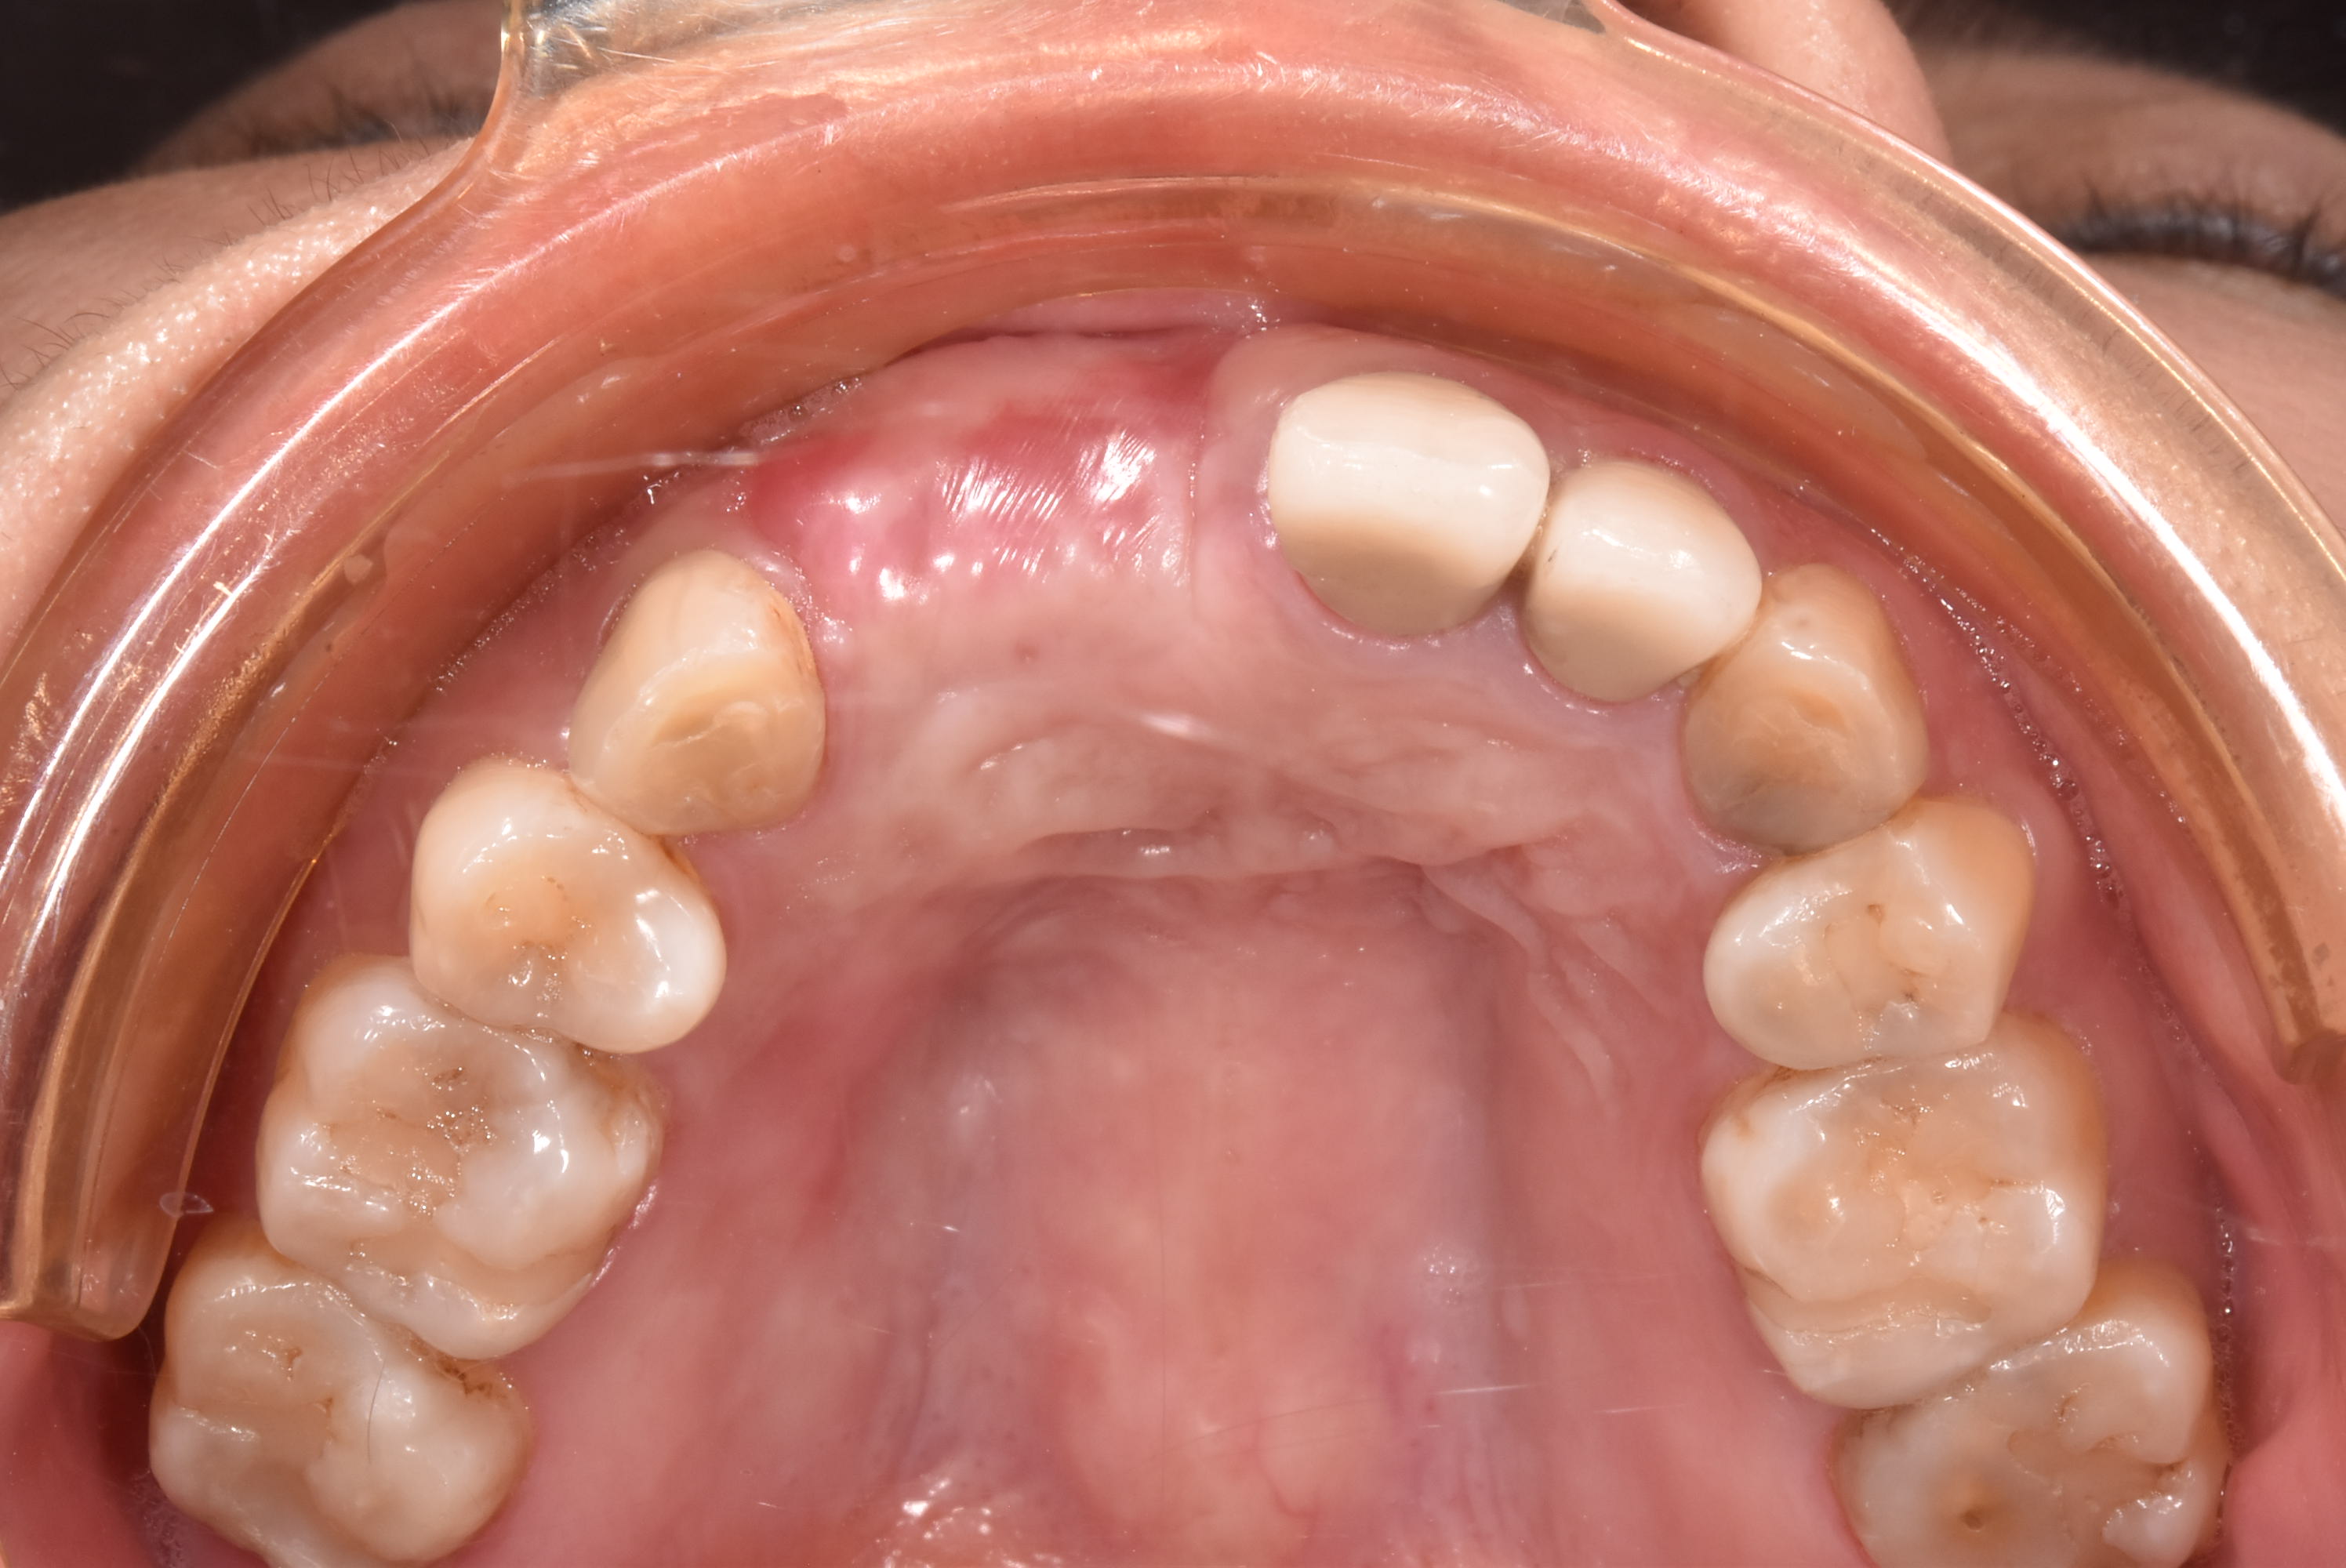

案例三